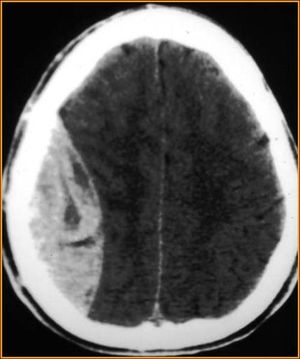

- Findings on CT are, classically, a lens (or lemon-shaped) shaped hyperdense lesion with sharp margins in the temporoparietal region

- Blood along the inside of the skull will not cross the sutures. This helps differentiate acute epidural hematoma from acute subdural hematoma.